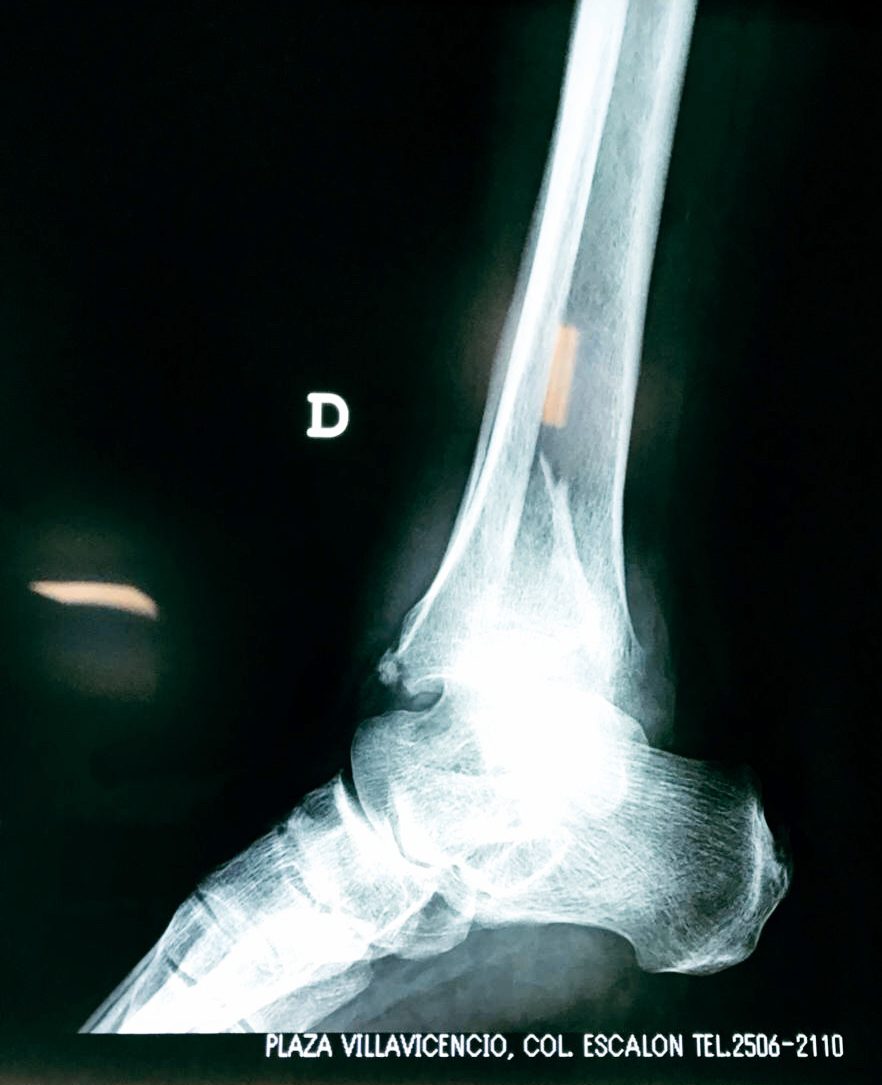

Una fractura de tobillo es la rotura de uno o más de los huesos del tobillo. Estas fracturas pueden ser:

Algunas fracturas de tobillo pueden requerir cirugía si:

- Los extremos de los huesos están desalineados entre sí (desplazados).

- La fractura se extiende hasta la articulación del tobillo (fractura intra-articular).

- Los tendones o ligamentos (tejidos que sujetan los músculos y los huesos entre sí) están rotos.

- El médico cree que sus huesos probablemente no sanen apropiadamente sin cirugía.

- El médico considera que la cirugía puede permitirle una recuperación más rápida y confiable.

- En los niños, la fractura involucra la parte del hueso del tobillo donde el hueso está creciendo.

Cuando se necesita cirugía, es probable que esta implique el uso de clavijas de metal, tornillos o placas para sostener los huesos en su lugar mientras la fractura se consolida. Los elementos de soporte pueden ser temporales o permanentes.